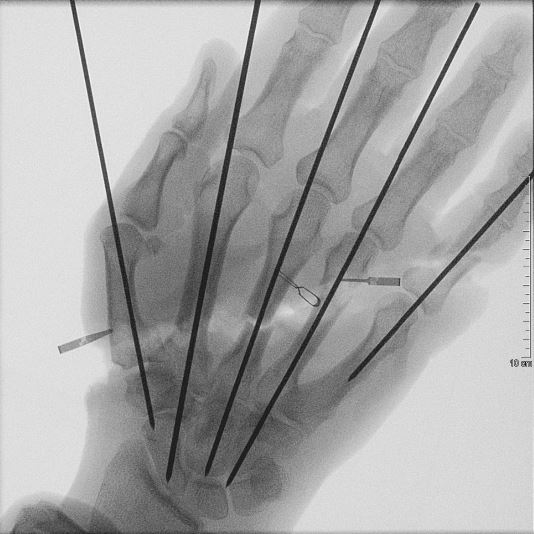

Die geröntgte Hand nach der Operation.  Bild: Bundeswehr Fotograf: Presse- und Informationszentrum des Sanitätsdienstes der Bundeswehr